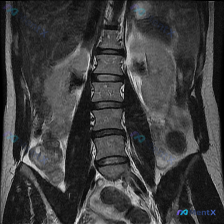

整理到一份腰椎MRI T2冠状位的影像资料,很有意思。 第一眼扫过去,视觉上似乎有点「脊柱侧弯」的感觉,但仔细看影像描述和序列本身——腰椎生理力线其实基本是正的,椎体序列也规整,没有明显的结构性侧弯。 真正跳出来的异常完全在别的地方: - 椎间盘有脱水变性,椎体边缘有骨赘(轻中度退变,这个不是重点)...

整理了一份影像+临床的讨论素材,感觉很容易踩思维坑: - 核心主诉/疑问:脊柱侧弯(Scoliosis) - 现有影像资料:单幅腰腹部冠状位T2加权MRI - 影像初步分析:双侧肾脏、肝脾、胆囊、膀胱、椎管内马尾信号均未见明显异常,无腹水/肿大淋巴结,报了“腰椎序列清晰”“未见明显病理学改变” 但仔...

整理到一张腰椎MRI T2加权像冠状位的资料,大家第一眼可以先看看: - 脊柱序列向左侧凸,顶椎大概在L2-L3水平,看起来有结构性改变 - 多个椎间隙(尤其下腰段)变窄,且凹侧更紧缩,椎间盘信号普遍减低 - 部分小关节区有骨赘、信号异常 - 椎体终板附近有斑片状信号不均 目前只给了这一个序列,你第...